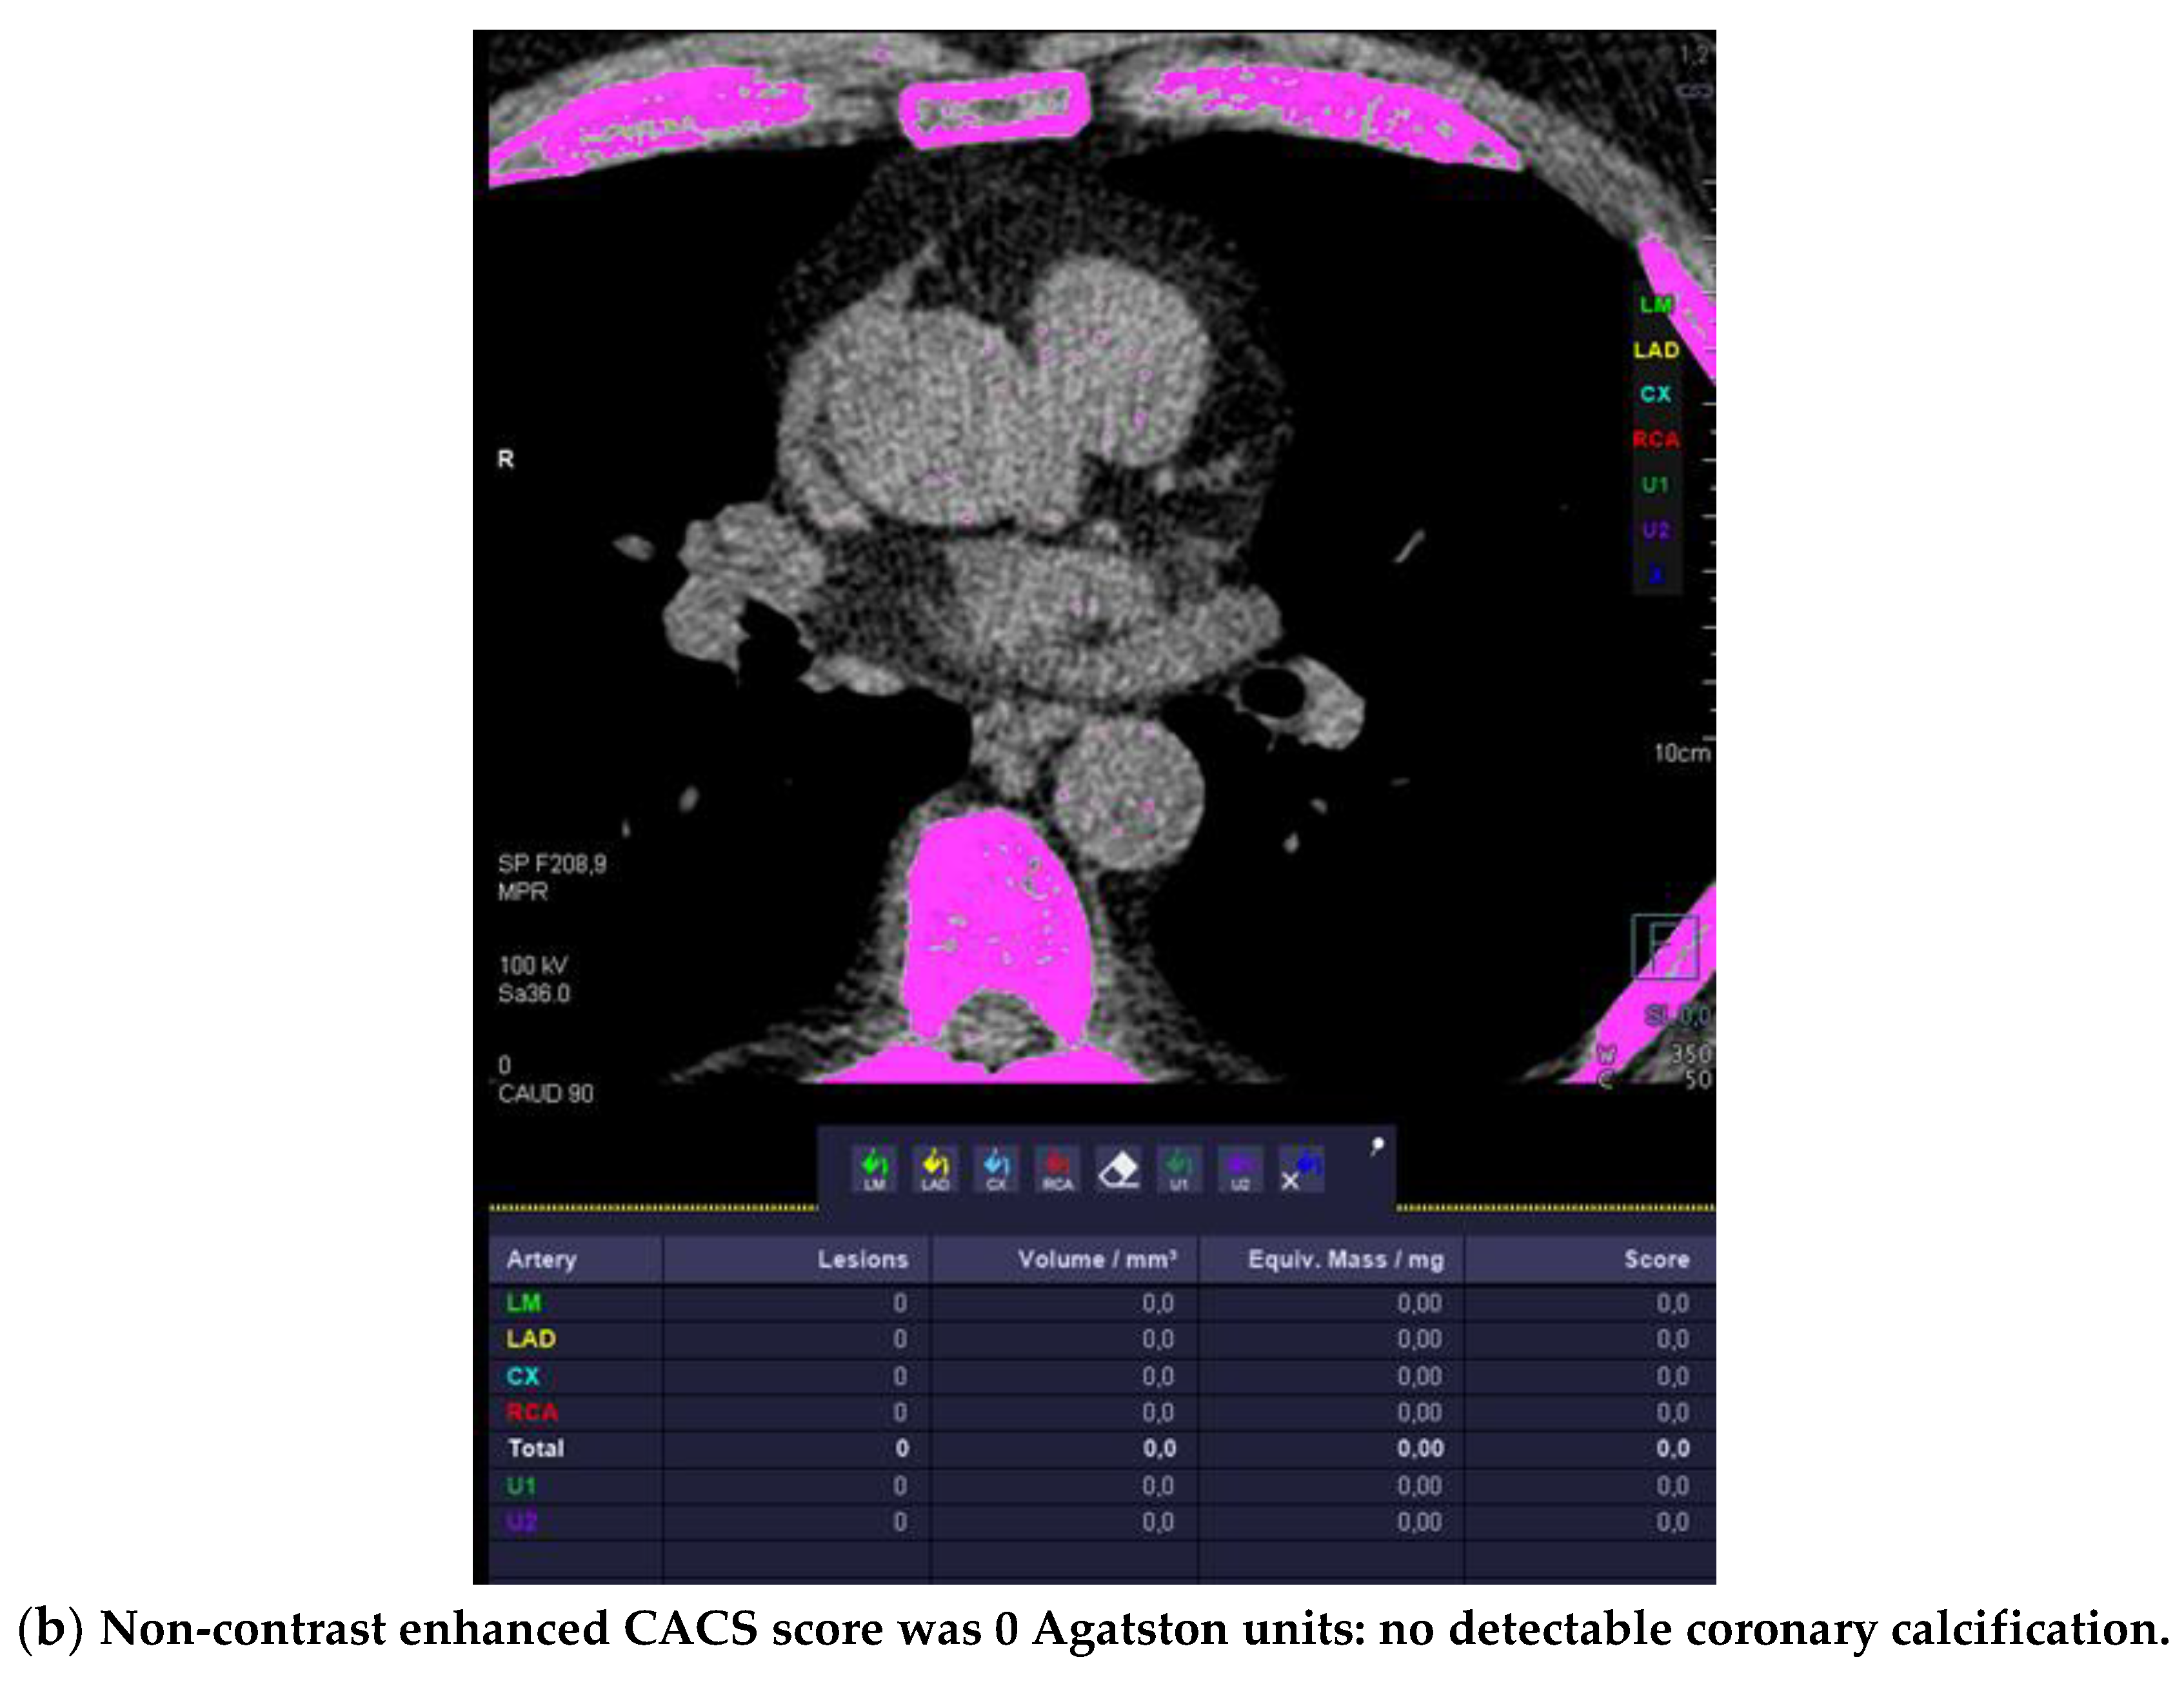

Out of those 103 with CAD and CACS 0, 52 (50.4%) had at least one HRP per patient (Figure 1).

Figure 1.

High-risk plaque (HRP) in a patient with CACS 0, a 70 years-old-male patient with ST-depression on ECG-treadmill stress test in V3-6. CT showed 37% diameters stenosis and a high-risk plaque (LAP 44 HU, positive remodeling) (white arrow) in the proximal left anterior descending artery (LAD), which were not detected by CACS (b). Diagnosis of non-obstructive CAD by CTA. Distal segment with deep myocardial bridging (MB), explaining stress test findings. (a) CTA (left: cMPR and right: 3-DVRT, spider view). LAD = left anterior descending. CX = circumflex artery.